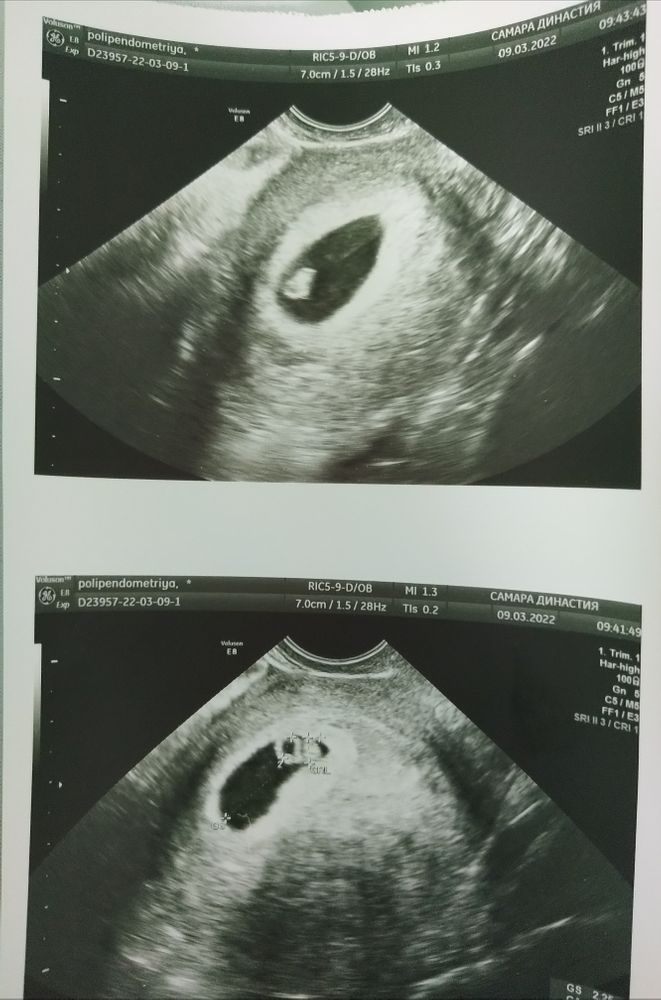

6 недель и 1/2 дня по УЗИ 💞

09.03.2022